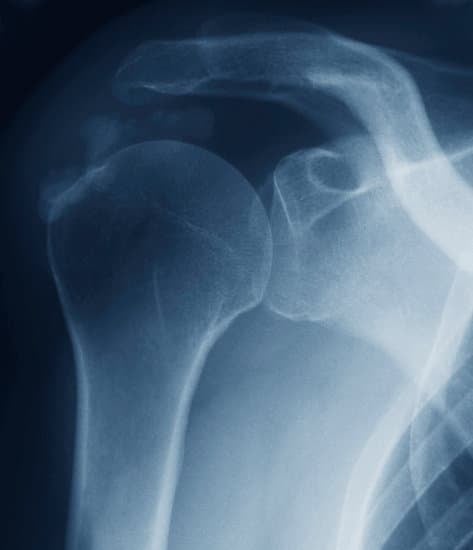

석회화 건염의 진단은 **엑스레이(X-ray)**와 같은 영상 검사를 통해 이루어집니다. X-ray를 통해 어깨 힘줄에 석회가 침착된 것을 확인할 수 있으며, 필요에 따라 초음파나 MRI로 힘줄의 상태를 추가적으로 검사할 수 있습니다.